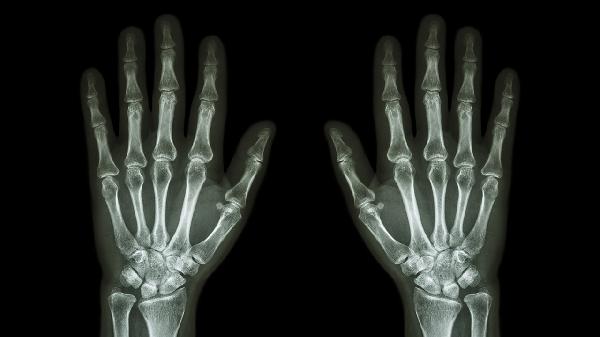

关节软骨退变引发的无菌性炎症,常见于中老年人群。晨起关节僵硬感明显,活动后疼痛减轻但过度使用会加重。X线可见关节间隙狭窄。可遵医嘱口服硫酸氨基葡萄糖胶囊、塞来昔布胶囊,配合关节腔注射玻璃酸钠注射液。